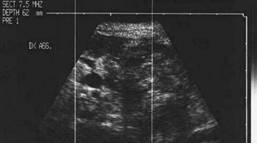

Sonda convexa de 5.0 MHz,

Sonda liniara de 10.0 MHz, proiectie trasversala si longitudinala a lobului

stang.

Pacienta de 28 ani. Voluminoasa tumefactie a lobului

stg., marcant hipoecogena, cu intarire posterioara, de 38x45x69mm.

La aspiratie, circa 60 cc de coloid foarte dens.